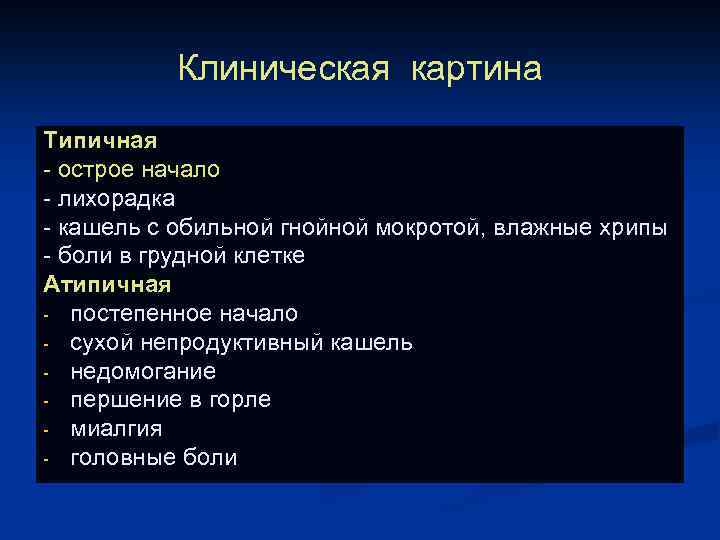

Клиническая картина Типичная - острое начало - лихорадка - кашель с обильной гнойной мокротой, влажные хрипы - боли в грудной клетке Атипичная - постепенное начало - сухой непродуктивный кашель - недомогание - першение в горле - миалгия - головные боли